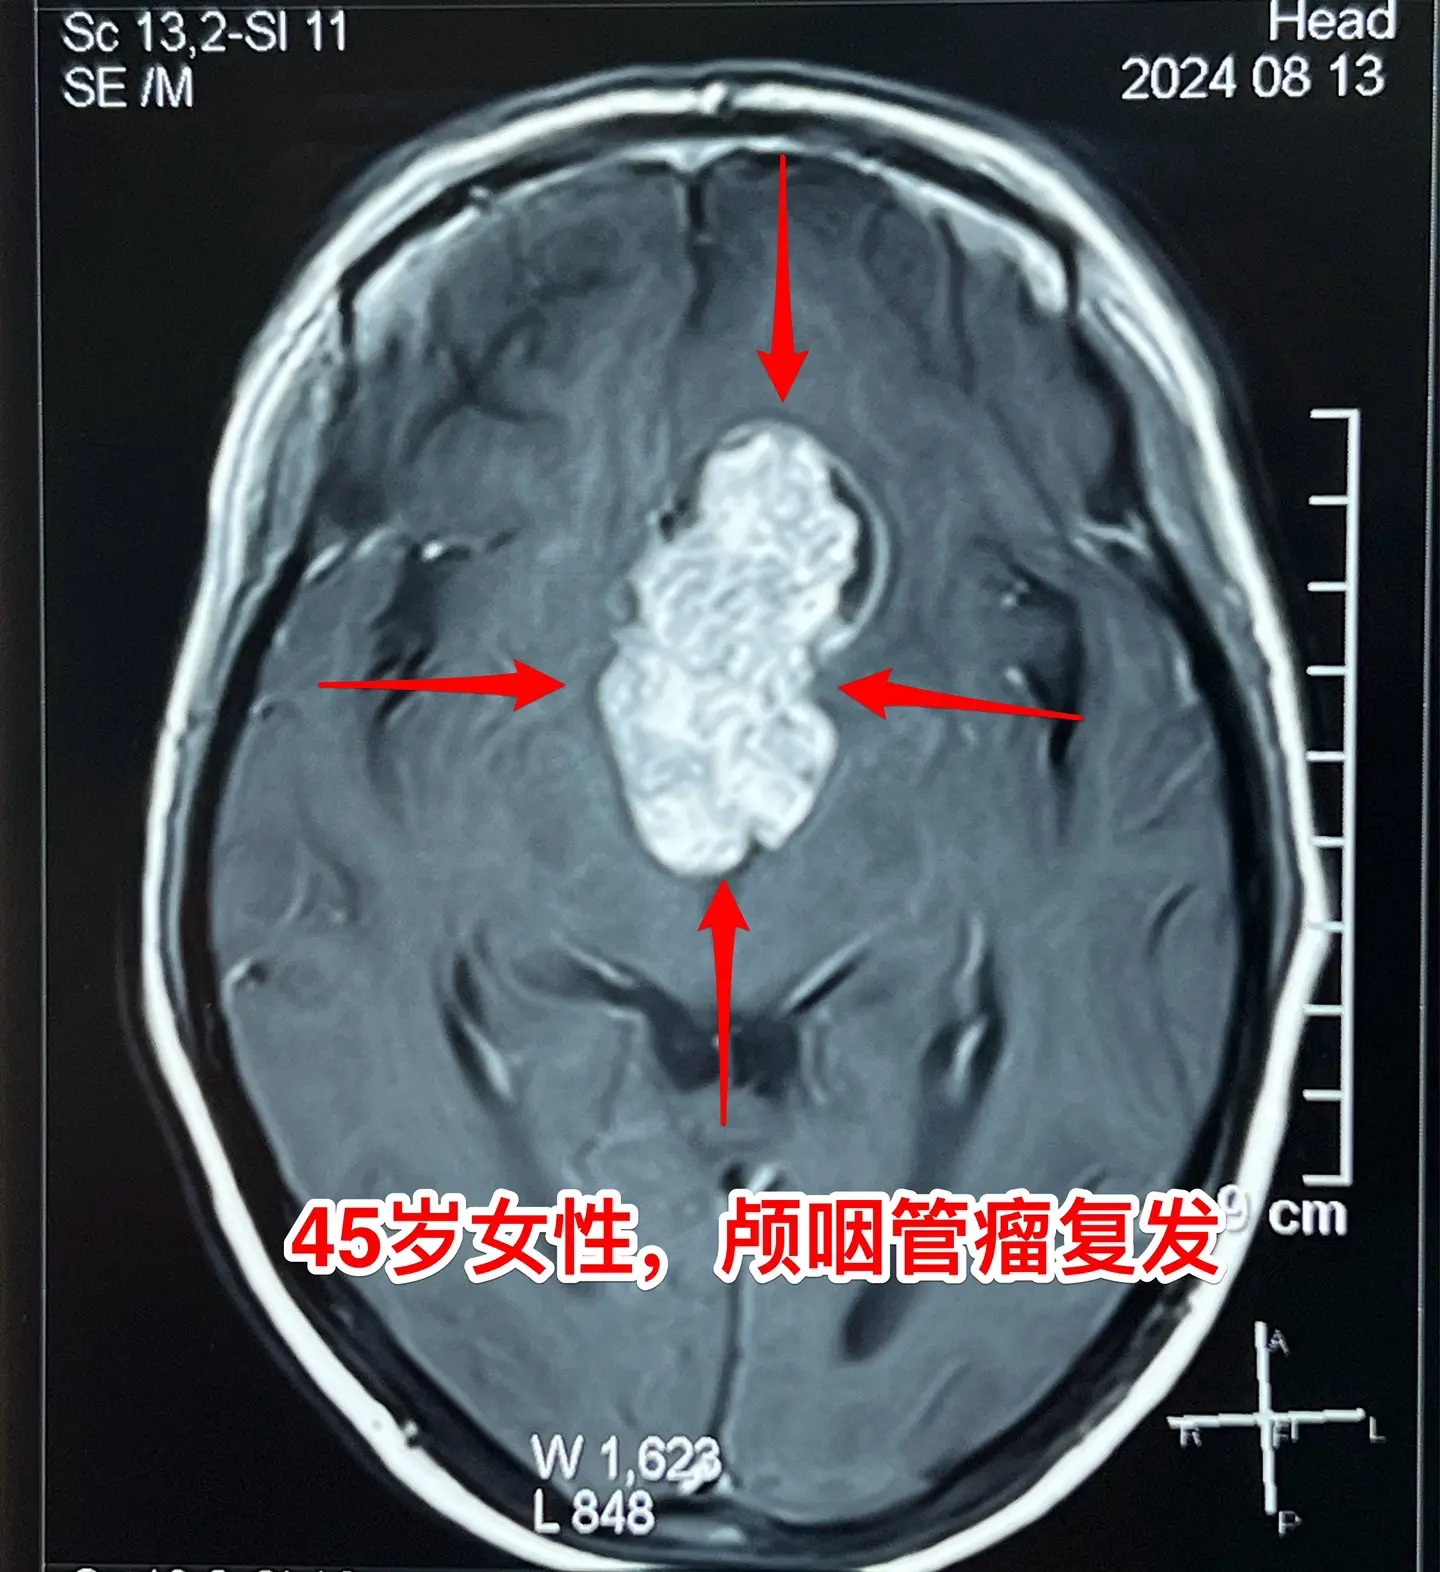

巨大的颅咽管瘤。45岁浙江女性,在外院作了颅咽管瘤手术不到一年,作磁共振显示肿瘤复发,而且体积巨大。 病人视力很差,记忆力也差,精神不好。 这么大的颅咽管瘤一般是需要作手术的。显而易见是这样的手术是很有难度的,很考验医生的技术和能力! 从影像学资料可以看出,这是乳头型颅咽管瘤。如果害怕作手术,对于运气好、经济状况好的病人,也可以试一试靶向药,也许有效。 这个病人选择了作手术!8月16日我们经过九个小时的紧张奋战,将肿瘤完全切除了。手术后CT结果很好。